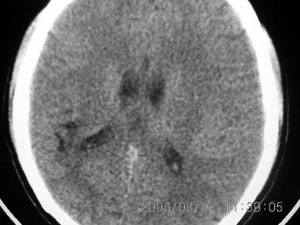

标题: CT4285:头部病变,女 21岁 [打印本页]

标题: CT4285:头部病变,女 21岁

女 21岁 发作性面色发白一年,每次发作仅数秒钟

脑血管畸形,建议做增强

脑软化灶可能性大.

局限性脑软化灶、脑萎缩,考虑动静脉畸形。

建议mri增强检查,不排除dnt可能。

局部软化灶,脑沟增宽加深,考虑为脑血管畸形可能,建议增强或mri检查.

左颞顶叶不规则低迷度影边界尚清楚,岁数年轻,应考虑脑血管畸形。建议强化或核磁,进一步检查。

考虑脑血管畸形可能,建议mr

局限性脑软化灶,右侧侧脑室后角受吸引,略有拉伸。考虑动静脉畸形。

首先考虑avm,但脑囊虫病有没有可能?